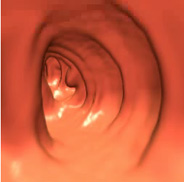

May 8, 2009 - The debate heats up amongst doctors in the advent of the Centers for Medicare & Medicaid Services (CMS) decision on reimbursement for virtual colonoscopy (also known as CT colonography or CTC). CMS will determine whether or not Medicare beneficiaries will have access to virtual colonoscopy, a noninvasive colon cancer screening procedure with the potential to increase low screening rates and save lives.

“I am writing to voice my strong disagreement with Medicare’s recent denial of coverage for virtual colonoscopy. We are all aware that colon cancer is a major concern to all American’s age 50 and older, that colon cancer kills more Americans each year than breast cancer and AIDS combined, and that appropriate screening is the only way to prevent colon cancer.

Medicine. Using updated technique and software, the results have been very clear…CTC is a valid, sensitive and safe modality for detection of polyps and cancer. The concerns over radiation and incidental findings seem to be a technique to detract from the real success of CTC. With new protocols and effective dose control the radiation dose is negligible, especially in this population of older patients. In well-trained hands the chance of significant incidental findings is approximately 3%. This is a low price to pay for effectively eliminating the risks and costs associated with screening optical colonoscopy. There has not been a reported perforation or bleed related to CTC. Incidental findings can be managed with the described C-RADS system; a system modeled after the BI-RADS system to classify incidental findings and their significance.

"This technology has the chance to be a life-changing event for many Americans. It will encourage more patients to be screened, which is the ultimate goal,” he said.